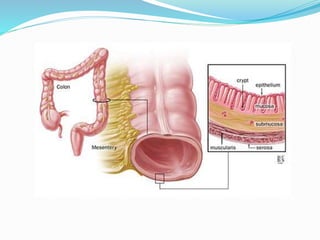

This document discusses colorectal polyps. It defines polyps and describes their types, including neoplastic and non-neoplastic polyps. It discusses adenomatous polyps in depth, noting their malignant potential increases with size over 1cm and villous architecture. Radiological diagnostic methods for polyps including single and double contrast barium enema and CT colonography are explained. The document provides an overview of polyp pathogenesis and genetic syndromes like FAP that increase cancer risk.